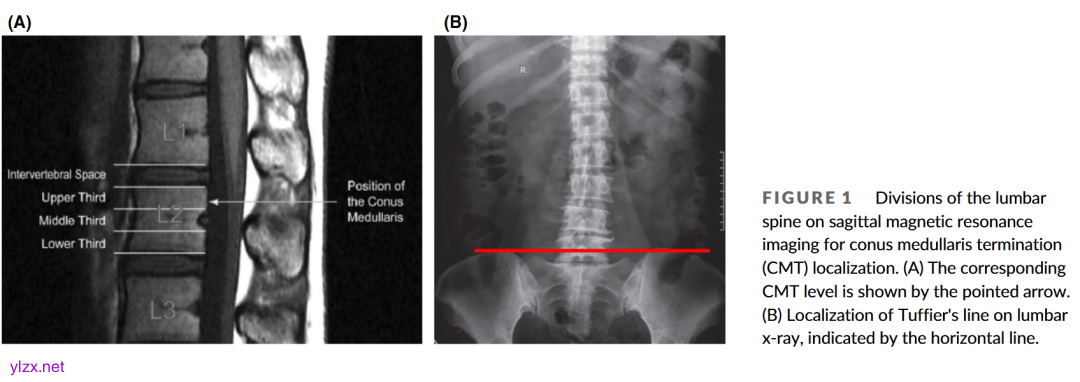

两位独立放射科医师评估CMT位置。CMT定义为脊髓末端最远点,按椎体上、中、下1/3及椎间隙划分(图1A)。通过腰椎正位X光确定TL(髂嵴最高点水平连线)对应的椎间隙(图1B)。其他数据收集:记录患者年龄、性别、身高、体重、BMI及脊柱病变(如椎间盘突出、椎管狭窄、脊柱侧弯等)。